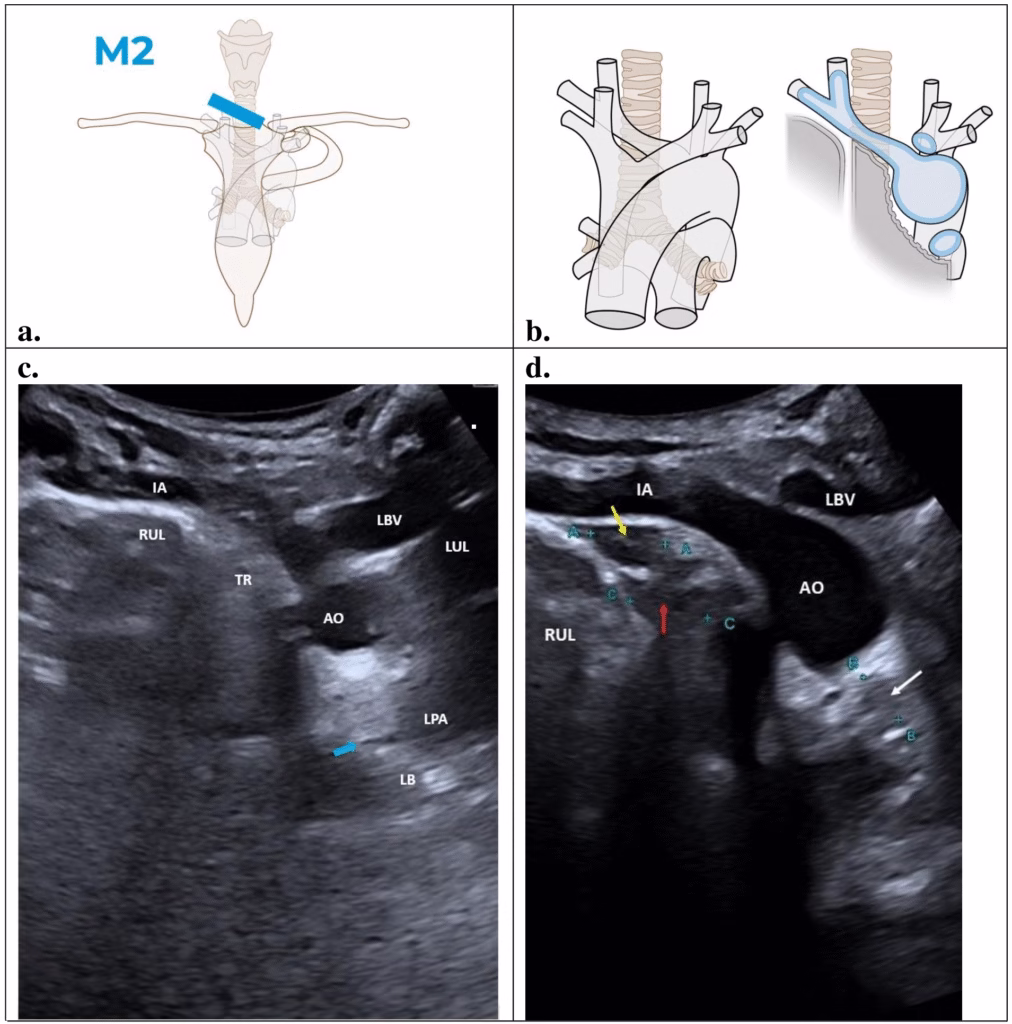

This section shows the paratracheal region between the upper right pulmonary lobe, the trachea, and the aortopulmonary region below the aorta. The probe should be placed in the suprasternal notch, on the right of the trachea, and angled downwards toward the mediastinum (Figure 3a). A slight compression can be applied on the right sternocleidomastoid muscle. Anatomically, this region is defined by the vascular landmark of the innominate artery, the right upper lobe pleural surface, the trachea, and the upper margin of left bronchus. These anatomical features should be included in this view, as depicted in blue in Figure 3b. The paratracheal region is a virtual space formed by the upper lobe’s pleural surface that contacts with the right wall of the trachea.

Figure 3. Oblique coronal view (M2): IA, innominate artery; RUL, right upper lobe; TR, trachea; AO, aortic arch; LBV, left brachiocephalic vein; LUL, left upper love; LPA, left pulmonary artery; LB, left bronchus. Illustrations prepared by Marie Delorme.

Figure 3b shows the key structural features of M2 section. A normal POCUS image of the suprasternal, oblique coronal view (M2) is shown in Figure 3c. An echogenic convex line from the pleural surface of the right upper lung lobe (RUL) can be seen on the right side of the scan. The innominate artery (IA) branches from the aortic arch and divides into the right common carotid and right subclavian arteries above the pleural line of the right upper lung lobe. A hypoechogenic imaging representing the shadowing artifact produced by the trachea (TR) lies at the end of the pleural line between the right upper lung lobe and the aorta. Additionally, the echogenic stepladder structures can be observed extending downwards from the trachea (blue arrow). These are the tracheo-bronchial cartilages which terminate below the aortopulmonary region. Tracheal and bronchial cartilage produces parallel echogenic stepladders, also known as “stair artifacts.”

The left brachiocephalic vein (LBV) is an anechoic structure above the left upper margin of the aorta. The anechoic left pulmonary artery (LPA) is located to the left of the aortopulmonary region. The artifact of the left upper lung lobe (LUL) is located to the left of the left brachiocephalic vein and left pulmonary artery. Aortopulmonary region is formed in this M2 section by an echogenic fatty triangle between the aorta, trachea-left bronchus (LB), and left pulmonary artery.

When lymph nodes appear in the paratracheal region there is a separation between the convex echogenic line from the right upper lobe and the hypoechoic artifact of the trachea. This convex echogenic line becomes a concave line. Lymph nodes are hypoechoic and sometimes confluent (yellow and red arrows) (Figure 3d). Lymph nodes can also be seen in the aortopulmonary region, which has a triangular shape in this M2 section above the left tracheobronchial wall (white arrow) (Figure 3d).